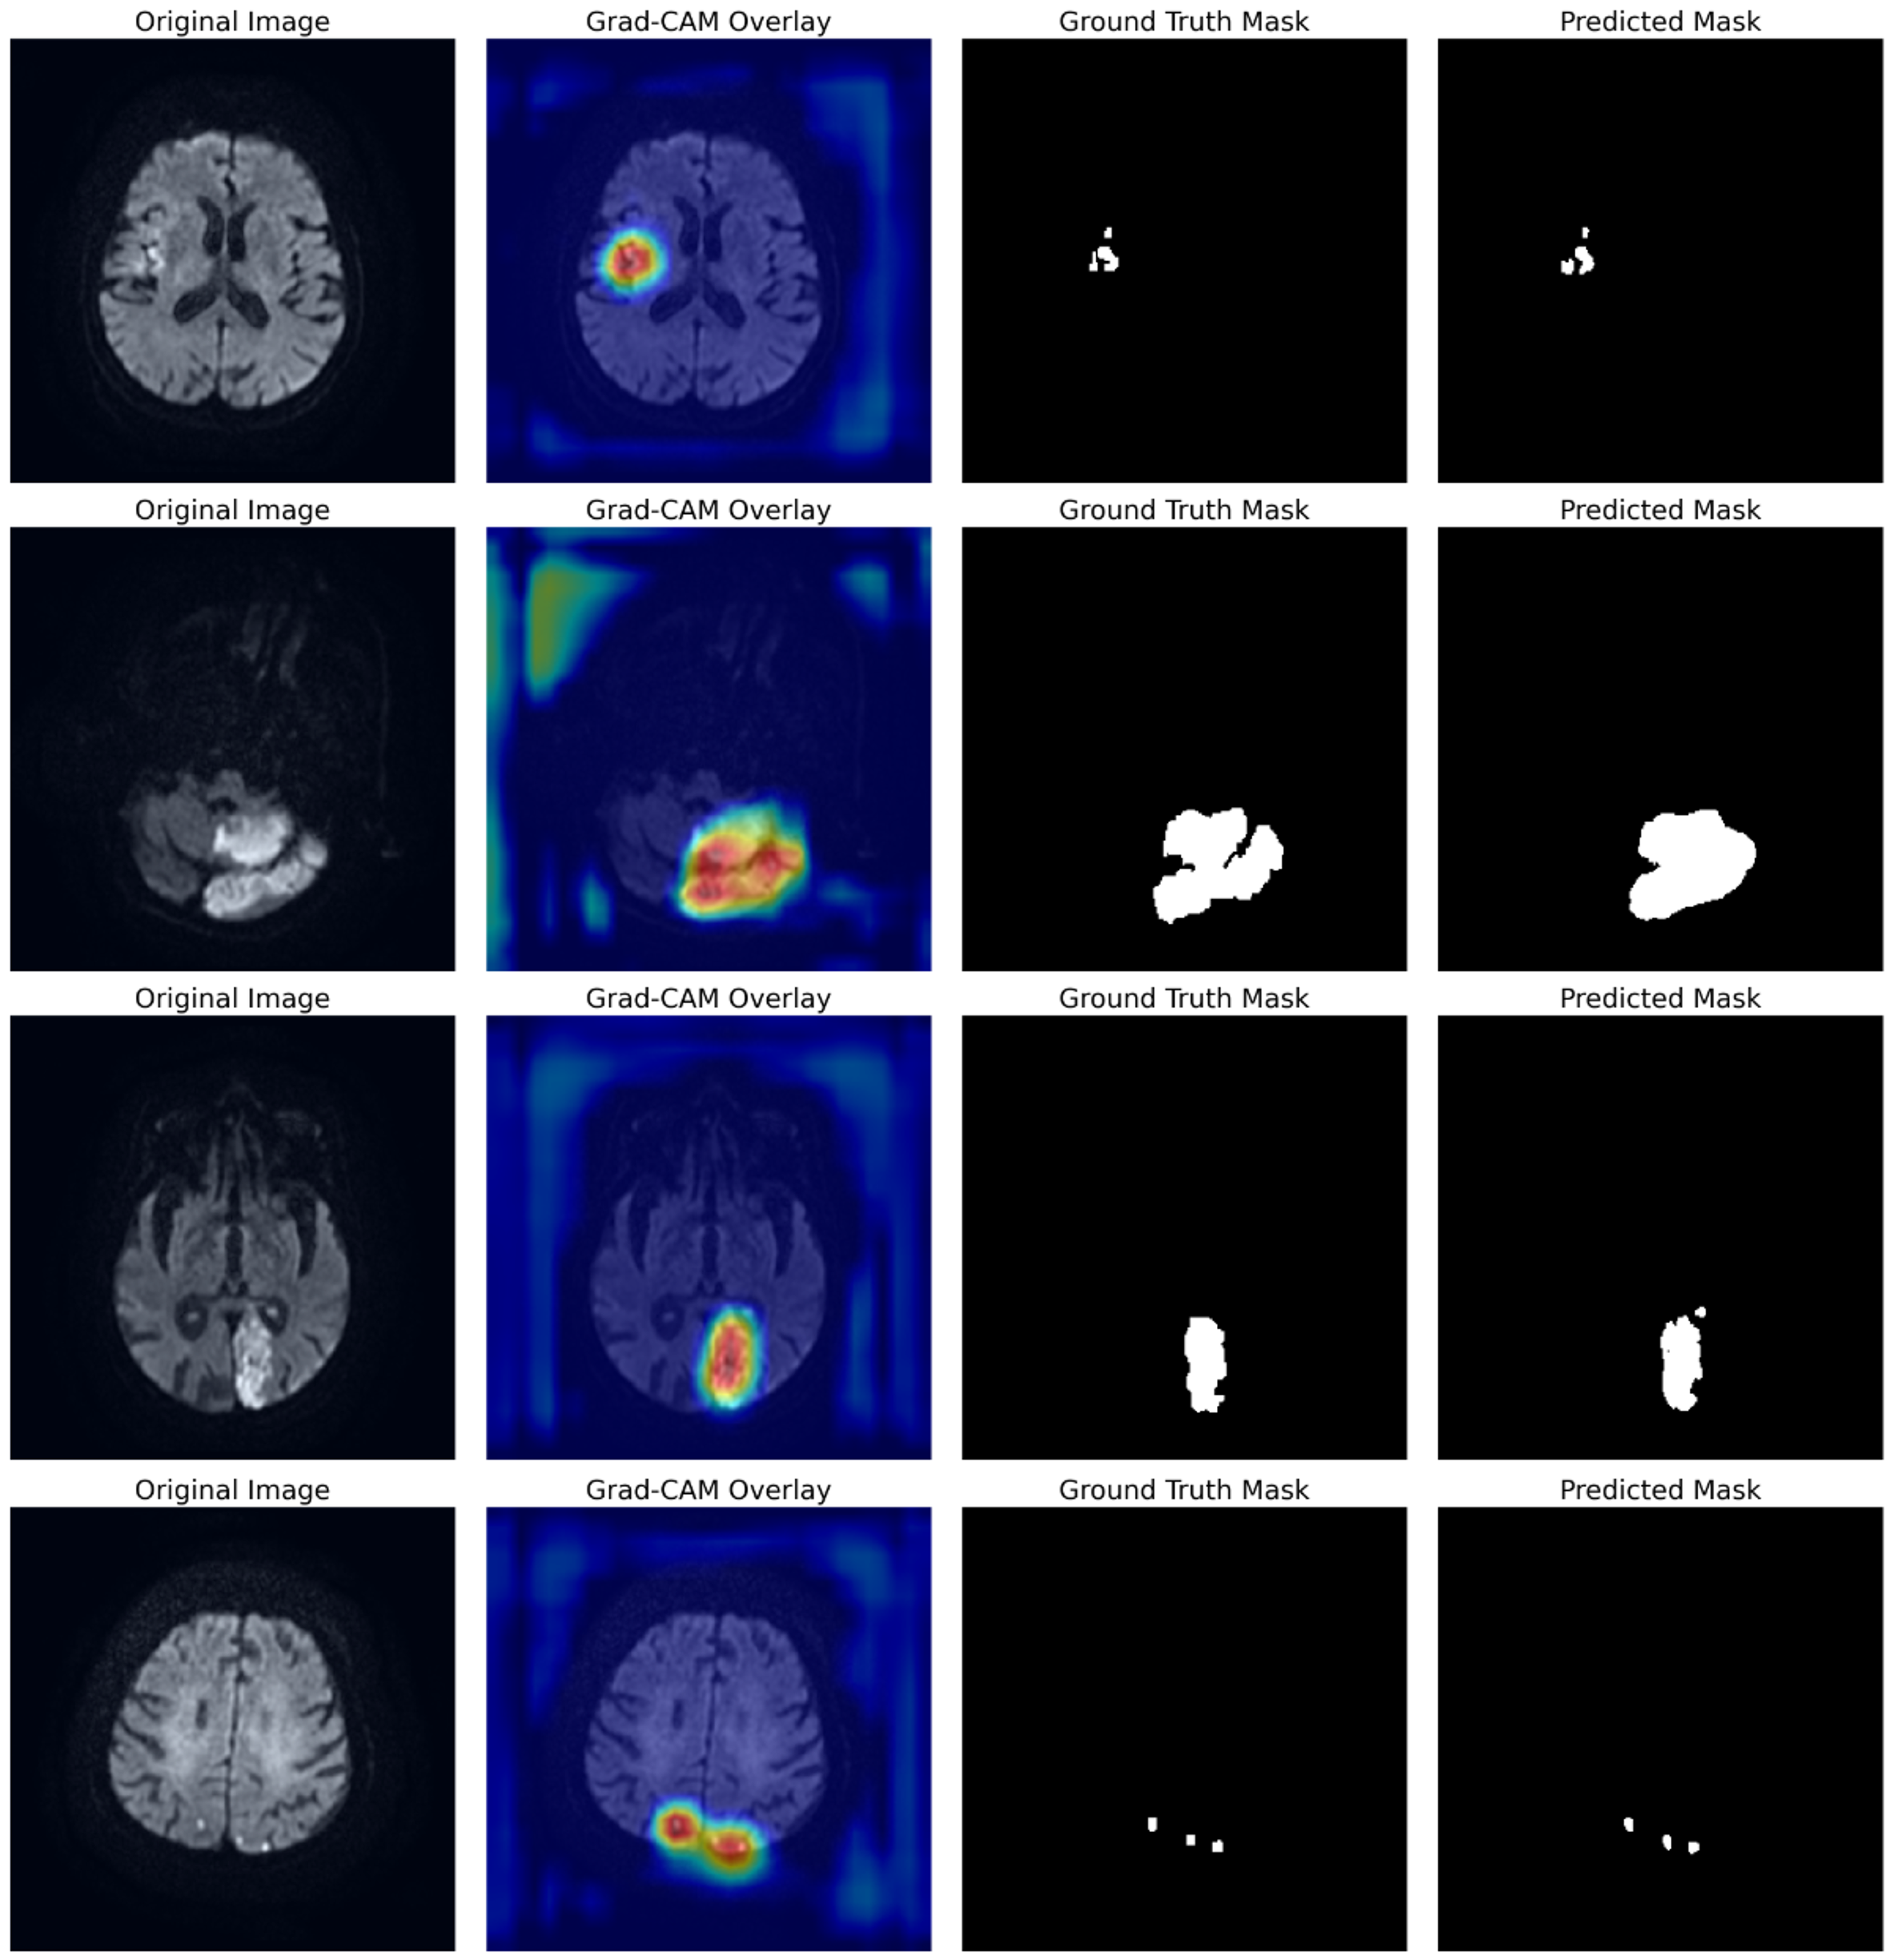

To move beyond quantitative metrics and gain deeper insight into the model’s interpretability, we employ Gradient-weighted Class Activation Mapping (Grad-CAM). This visualization technique produces heatmaps that highlight the image regions most influential in the model’s segmentation decision. Fig. 5 depicts the Grad-CAM heatmaps for representative cases from the test set. By analyzing the heatmaps from the FA-UNet, we qualitatively assess whether our architectural enhancements effectively guide the model’s focus toward the true pathological areas.

Fig. 5.

Visualization of FA-UNet’s learned attentional focus using Grad-CAM. Each row displays a different test case, showing the Original Image, the Grad-CAM heatmap overlay, the Ground Truth, and the final Predicted Mask. The heatmaps (red/yellow) highlight the model’s focus, which is consistently localized on the true lesion areas. Grad-CAM, Gradient-weighted Class Activation Mapping.

The analysis in Fig. 5 provides compelling visual evidence of FA-UNet’s robust localization capabilities. Across all presented cases, which include lesions of varying size and morphology, the model’s attentional hotspots (red/yellow) show a remarkable correspondence with the ground truth masks. For instance, the model accurately focuses on the entirety of larger infarcts (rows 1–3) as well as smaller, distinct lesions (row 4), confirming that it has learned to identify relevant pathological features rather than background noise. This direct correlation between the model’s learned focus and the final segmentation output underscores its reliability and provides a basis for clinical trust.